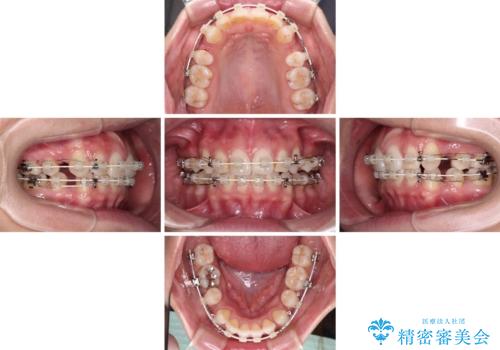

- 矯正装置

- 審美装置

- 1年7ヶ月

- 10-30回

- くちばしのような前歯の突出感を気にして来院された患者様です。

上下左右第一小臼歯4本を抜歯して、積極的に口元を引っ込めるよう、ワイヤー装置にて矯正治療を行うこととしました。